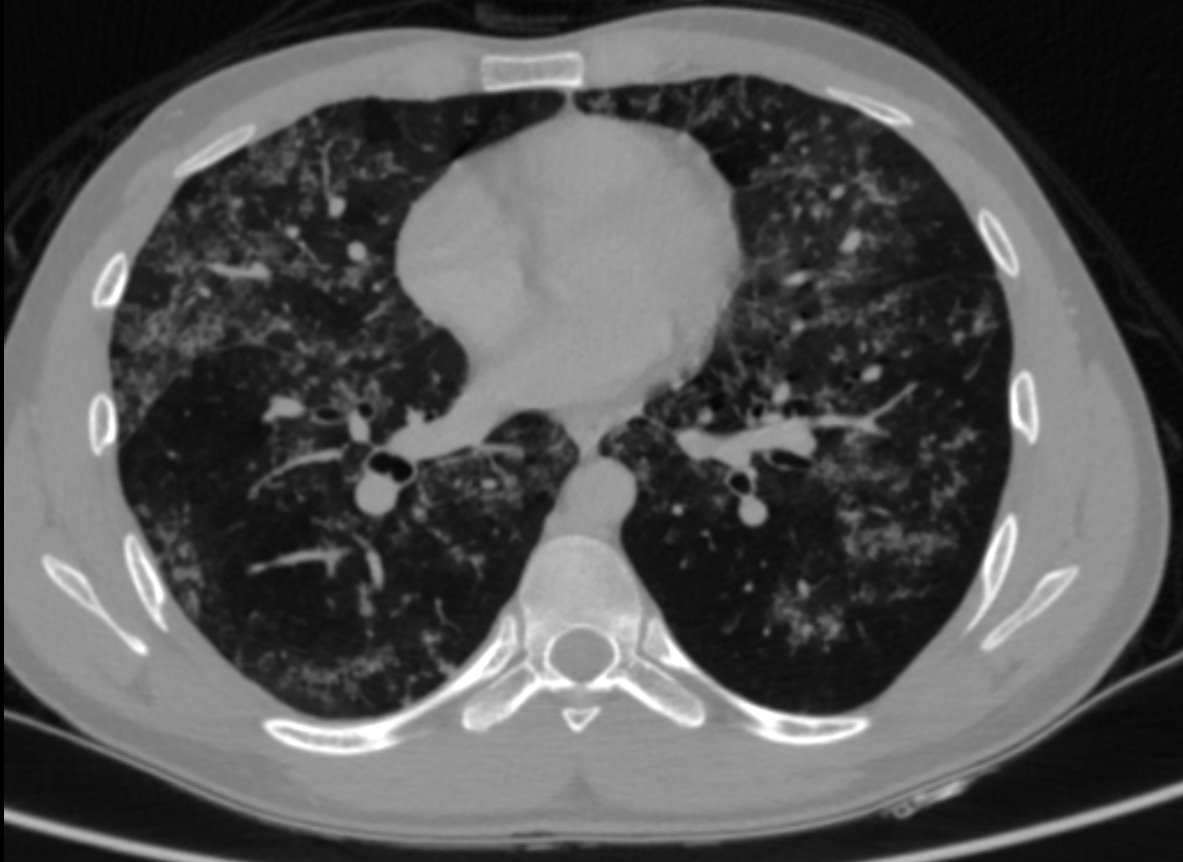

A 23 year old male presented with cough and dyspnoea since 3 months.

• HRCT thorax was performed.

• Numerous patchy nodular parenchymal infiltrates distributed diffusely in all the lung lobes, with a peribronchovascular and subpleural distribution.

• Apical emphysematous changes.

• No significant mediastinal lymphadenopathy seen. No effusion

• Alveolar sarcoidosis

Alveolar sarcoidosis is an atypical pulmonary manifestation of sarcoidosis.

This appearance is thought to result from the aggregation of a vast number of interstitial granulomas rather than representing a true alveolar process.

1.Appearance of alveolar sarcoidosis opacities:

• Patchy lung opacities 1–4 cm, rounded or elongated

• Irregular, blurred margins, may show air bronchograms

• Located along bronchovascular bundles or subpleural

2. Characteristic signs

• Galaxy sign: opacity with many surrounding small nodules (granulomas)

• Fairy ring / Reverse halo: circular arrangement of opacities with central clearing

3. Associated CT findings

• Nodules, ground-glass opacities,

• Thickened bronchovascular bundles,

• Thickened interlobular septa